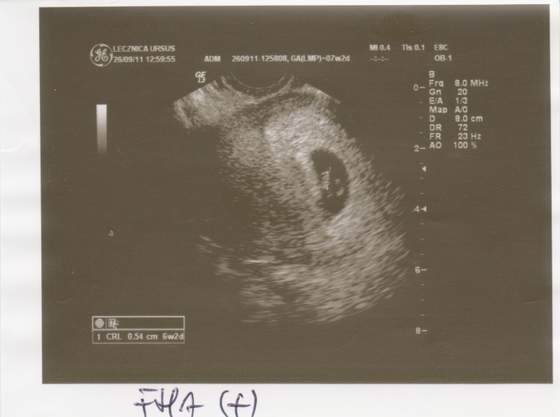

Zobacz załącznik 393882

nasza Kropeczka :-) ma 6 tygodni i dwa dni oraz 5,4 mm długości, serduszko już bije:-) i na razie wszystko jest dobrze